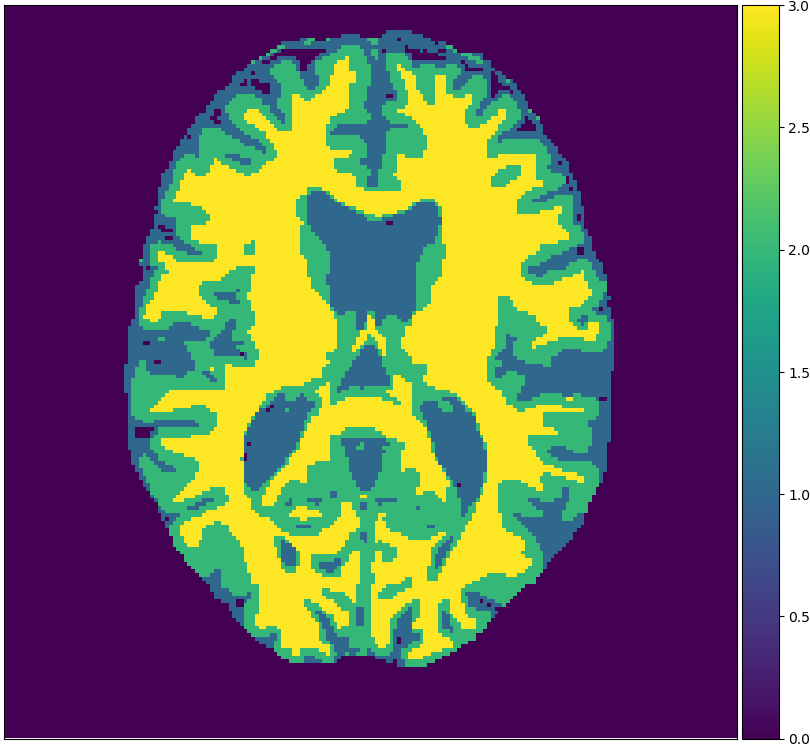

We will make use of 3 publicly available data sets: Brainweb1.5T, MRBrainS13, and IBSR. Each data set originates from one medical center. Brainweb1.5T is based on 20 realistic phantoms from Brainweb [2] and an MRI simulator (SIMRI; [3]). The simulator was set to use TE, TR and flip angle parameters of the 1.5T scanner in the Rotterdam Scan Study [9]. MRBrainS13 is a grand challenge for medical image tissue segmentation methods containing 5 scans for training [14]. The scans are 3T and have been fully manually annotated. IBSR is a classical data set of 18 patients and is automatically segmented but manually corrected [18]. Skulls are stripped off in all scans. Figure 1 visualizes examples from these sets.

Figure 2 shows examples of each segmentation method on the MRBrainS13 data set, with Brainweb1.5T as the source center. For the unsupervised models we only show boundaries between clusters, to indicate that interpretation remains a necessary step. A couple of observations can be made: firstly, the hidden Potts models produce smoother segmentations. Secondly, the U-net over-predicts white matter in the whole image. Thirdly, the 1-nearest-neighbours classifier over-predicts background voxels in fluid regions. Lastly, all methods favour white matter over gray matter in ambiguous regions.